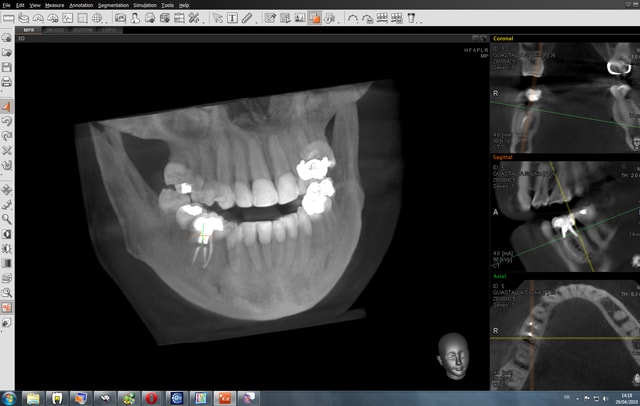

Bon finalement j'ai fait mon choix, cone beam installé hier !

Vatech Ewoo.

Pour moi les plus :

- taille de champ variable: 5*5 8*5 8*8 12.5*8

- vraie combo pano/cone beam

- interface sympa

- artefact métallique limité

- Logiciel d'imagerie et planification implantaire très bien

(pour info c'est une version d'Ondemand3D à l'essaie pour 90j ici:

http://www.ondemand3d.com/Content/Download/Trial.aspx prix du soft environ 5000$)

- budget compétitif

quelques clichés d'essais